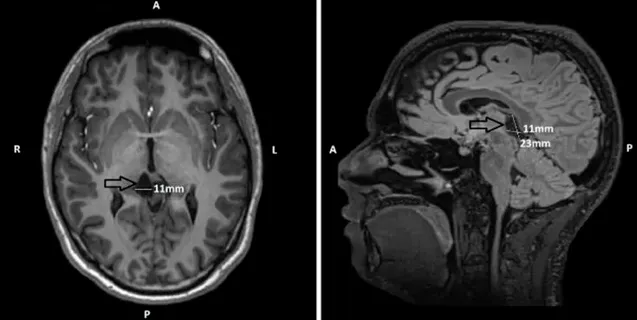

检查结果出乎所有人员预料:一个蛛网膜囊肿,正持续对小米的丘脑及中脑顶盖区域形成压迫——该区域恰为大脑调节警觉性与注意功能的核心枢纽。

持续长达十年的嗜睡症状,其根本原因可能即在于此。

两个月后,小米接受了神经外科手术治疗。INC教授团成员Henry W.S. Schroeder教授及其医疗团队主刀,采用显微开窗技术,精确解除了囊肿对脑组织的压迫效应,恢复了脑脊液正常循环通路。手术过程顺利成功。

术后半年复查时,磁共振成像清晰显示:囊肿体积已显著缩小,中脑区域的压迫完全解除。更为重要的是,小米自觉“如同获得新生”。